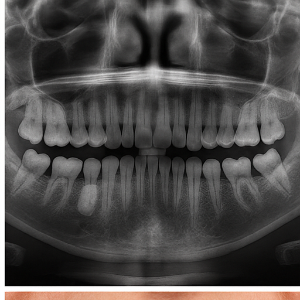

치과 방사선(X-ray) 촬영

시각적 검사만으로 충분한 경우도 있지만, 필요할 때는 엑스레이 촬영도 사용됩니다. 일반적인 파노라마 X-ray나 치아 전체를 보는 엑스레이 사진에서는, 하얗게 나타나는 골융기 형태가 확인되기도 해요 .

이 방법은 단순한 확인뿐 아니라, 혹시 다른 뼈나 조직의 이상과 착각할 수 있는 질환(종양 등)을 구분하는 데도 도움을 줍니다 .